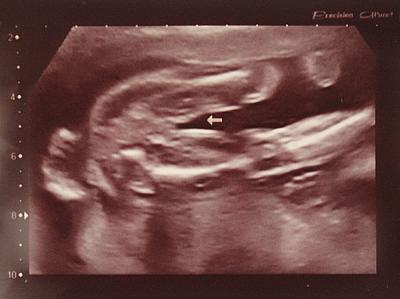

Gehöre auch zu euch hier ins Juni Forum mein Wurm soll am 12.6 das Licht der Welt erblicken. Bin derzeit auch nicht so aktiv hier im Forum. Habe ganz am Anfang mal mit geschrieben aber jetzt ein weile eben so gar nicht. Lese aber immer fleissig mit. Dazu muss ich sagen ich habe hier 3 Kids zu Haus und der kleinste ist gerade 1 Jahr alt geworden. Da bleibt so einiges auf der Strecke. Würde jetzt aber dennoch gerne einmal eure Meinung wissen. Ich hatte am Donnerstag FD und dort meinte die Ärztin ob wir wissen wollen was es wird. Wir natürlich mit Ja geantwortet. Dann hielt sie das US-Bild an und meinte na was sehen sie. Ich dann so, ich sehe gar nichts. Mein Mann hat auch nichts gesehen dann sagte ich zu ihr, ist es evtl. ein Mädchen und dann nickte sie nur und sagte ja das wird ein Mädchen von einem Schniepel keine Spur. Sie musste sich wirklich sehr sicher sein. Denn am Anfang der FD hatte sie schon ein Bild mit nem Pfeil makiert und ausgedruckt ohne uns etwas zu sagen. Am Ende gab sie uns denn das Bild. Da hatte sie gleich am Anfang schon das Outing eingefangen. Dennoch bin ich mir unsicher. Man hört immer soviel und da ich mir ein Mädchen wünsche habe ich Angst nachher enttäuscht zu werden. Wie seht ihr das? Wie sicher ist das Outing bei der FD in der 22 SSW? Habt ihr alle eindeutig das Mädels-Outing gesehen? Bei meinem Sohn war das so eindeutig da zweifelte ich nicht. Hänge euch mal das Bild ran welches die Ärztin uns mitgegeben hat. Mit Pfeil. Bin auf eure Meinungen gespannt. Lg

Bild zu Frage an die Mamis mit Mädel-Outing - Forum für Juni - Mamis

Das sieht ziemlich eindeutig aus. Man sieht ja nicht nur "keinen Schniedel" sondern Schamlippen. Sah bei meinen bald 3 Mädels auch immer so aus.

Ich denke bei der FD in der 22. SSW ist das Outing sehr sicher. Und zum Bild: eindeutig Mädchen. Habe mehrere Bilder meiner Tochter, die genauso aussehen. Jetzt erwarte ich auch wieder ein Mädchen und auch von ihr gibt es schon Bilder, die genauso aussehen, wie das, was du eingestellt hast. Laut Aussage meiner FA sind auch die beiden hellen parallelen Striche eindeutige Hinweise für eine Scheide bzw. Schamlippen.. Also - freue dich ruhig :-) LG Babynummerdrei